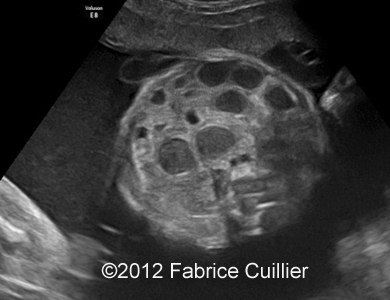

At 32 weeks, the aspect of the intestinal dilatation changed. Low digestive obstruction was suspected (Image 2, 3), with important aggravation at 35 weeks (Image 4). Mesenteric artery and vein had a physiological position (Image 5). Fetal ears and face were normal. Corpus callosus was present (Image 6). The extremities were also normal. Sex was male with bilateral hydrocele (Image 7). Abdominal fetal MRI was performed (Image 8, 9).

Image 2, 3: Slightly intestinal obstruction at 32- 33 weeks.

3A

3B